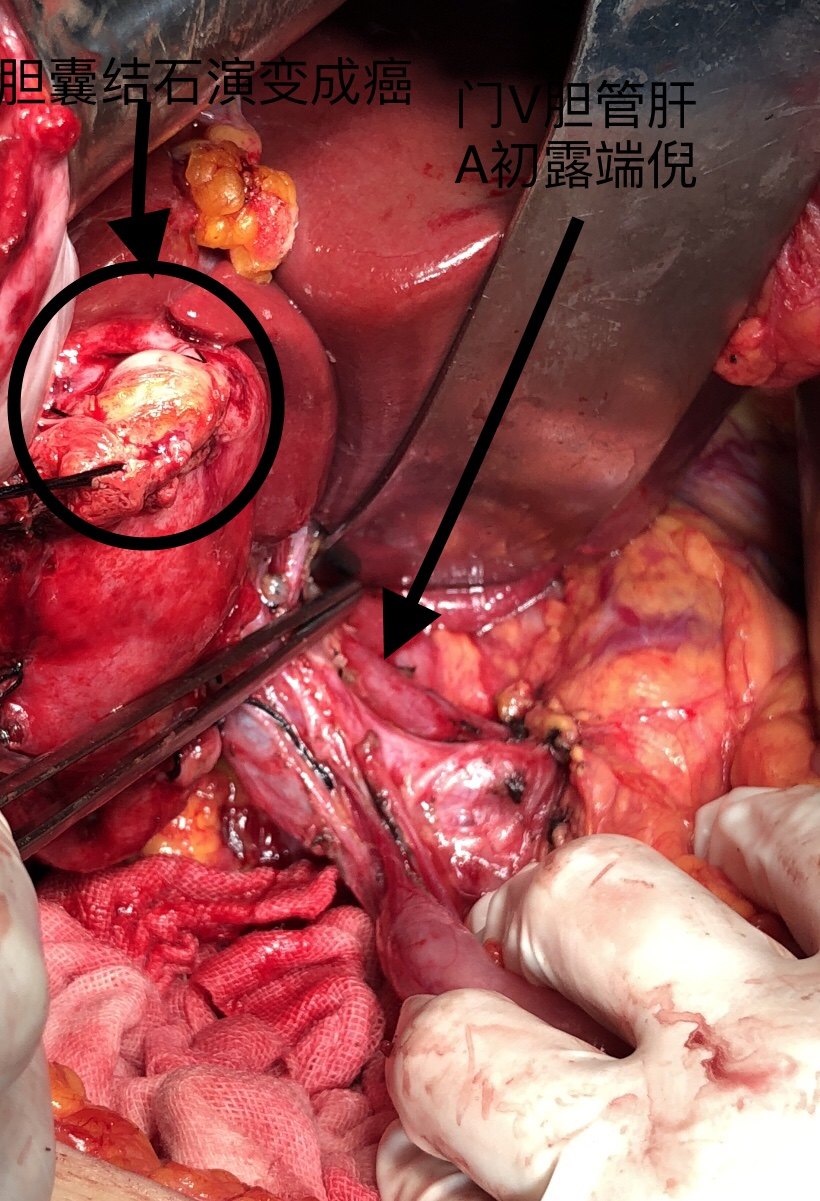

天使之手:手起刀落,肿瘤不留,钦州市第一人民医院肝胆外科今日完成一

图片尺寸640x854